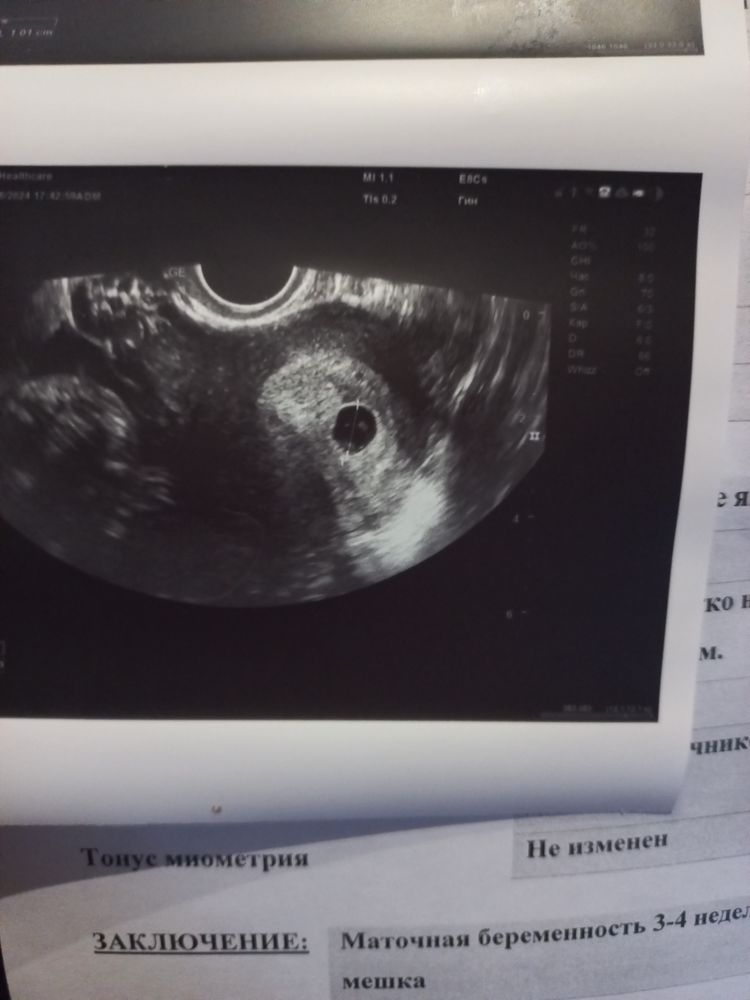

Пошла на узи спустя ровно 7 дней. Вся история есть в дневнике, но если кратко, то по предыдущему узи выявили слабый рост плодного яйца (всего 3 мм за 9 дней). Снимок и протокол узи этого дня на фото 1 и 2 соответственно.

Сегодня пошла ровно через неделю. Что мы имеем? Плодное яйцо абсолютно не выросло. Так же и осталось 1 см. ЖМ уменьшился, но будто наоборот он стал нормальным. И увидели что-то похоже на эмбриона, но это не точно. Ещё и хорион узиста смутил. Снимок и протокол будет на фото 3 и 4 соответственно.